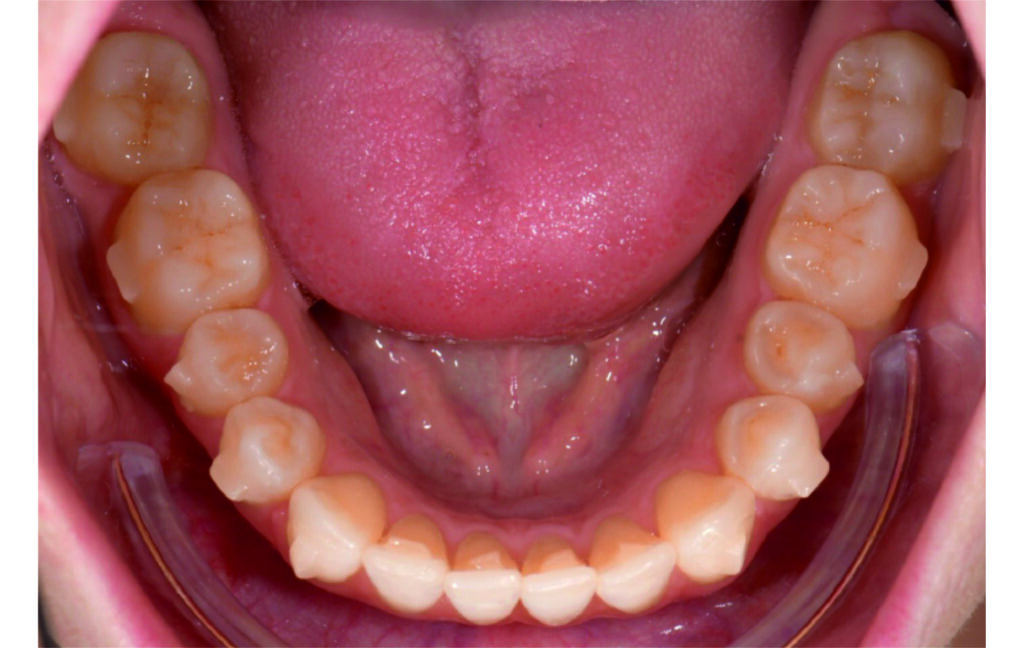

Angle Class II 2mm on the right, Angle Class II 2mm on the left, light mandibular asymmetry to the right, lower central line 1mm to the right, upper central line 1,5mm to the left, 1mm overjet and overbite. Sagittal asymmetry of upper dental arch. Light crowding upper and lower frontal segments, severe attrition of posterior teeth, night bruxism. Normal sagittal position of both jaws, high angle case, steep mandibular ramus,excessive lower facial height, open bite tendency.

The case initially presented as a moderate Class II on the right and a Class II tendency on the left, with tapered dental arches and an anterior open bite extending to tooth 26 in segment II.

In segment I, the open bite reached up to the first premolar.

No sequential distalization for Class II tendency correction was performed due to skeletal anchorage. Lingual attachments were used to improve aligner grip and control tooth movement, as small, angulated lower incisors are difficult to move due to limited anatomy.